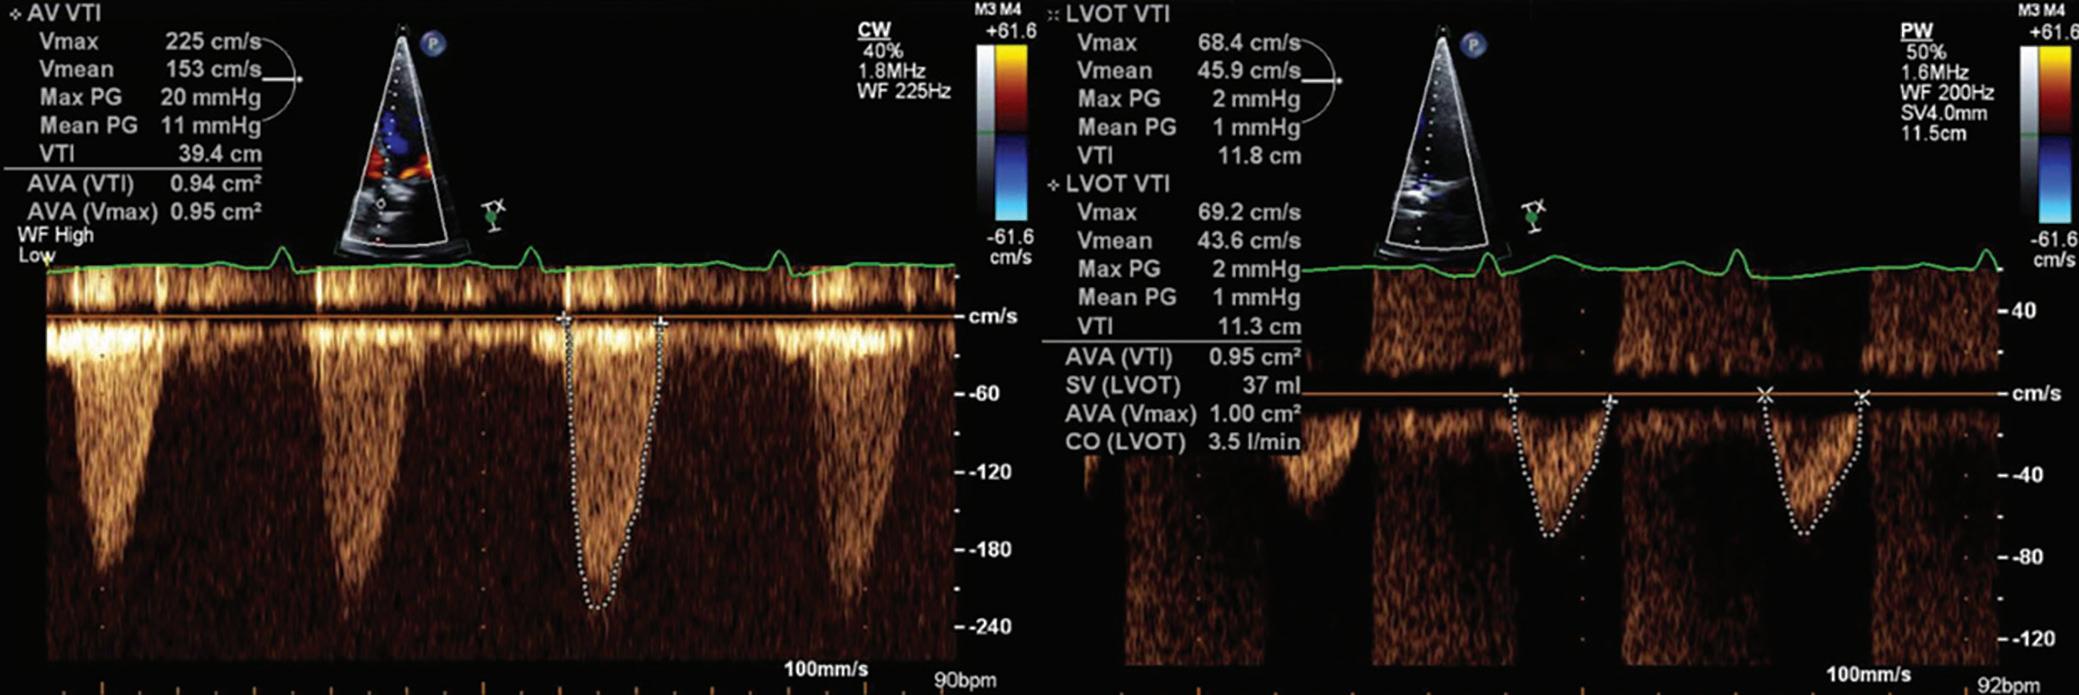

Presentation: A 64-year-old man with type 2 diabetes with neuropathy and active tobacco use presented to a local hospital with weakness, fatigue, dyspnea on exertion, paroxysmal nocturnal dyspnea, orthopnea, leg swelling, and abdominal distention. He had been diagnosed with moderate aortic stenosis (AS) seven years earlier. One year earlier, the patient was able to work full-time on home renovations with heavy lifting, but since that time he had developed class IV symptoms.

Hospital Course: Physical exam revealed massive peripheral edema and ascites. Transthoracic echocardiogram showed severe biventricular failure and aortic valve Doppler findings consistent with low-flow lowgradient aortic stenosis (Figure 1). Hemodynamic optimization was attempted with IV diuresis and paracentesis with removal of 5 l of ascites, but the patient developed significant hypotension and was started on a dobutamine infusion with only temporary improvement.

Subsequent right heart catheterization revealed a cardiac index of 2 l/min/ m2 on a dobutamine infusion of 3 µg/kg/min. Coronary angiography revealed critical right coronary ostial obstruction with no other obstructive coronary artery disease. Further hemodynamic deterioration led to transfer to a tertiary care center. Intra-aortic balloon pump (IABP) placement was attempted prior to transfer but could not be accomplished because of severe iliac obstruction.

On transfer the patient was hemodynamically stable on 10 µg/kg/min of dobutamine and 0.08 µg/kg/min of norepinephrine with a cardiac index of 2.7 l/min/m2. Repeat echocardiogram confirmed left ventricular ejection fraction (LVEF) <20%. Invasive assessment confirmed aortic stenosis with an area of 0.93 cm2 at both 2.5 and 10 µg/kg/min of dobutamine with augmentation of the aortic valve mean gradient from 17.6 to 27.4 mmHg. Aortoiliac angiography revealed left common iliac origin occlusion and right common iliac severe calcific obstruction.

Figure 1: Transthoracic Echocardiogram Doppler Studies of the Patient’s Aortic Valve Demonstrating Low-flow Low-gradient Aortic Stenosis